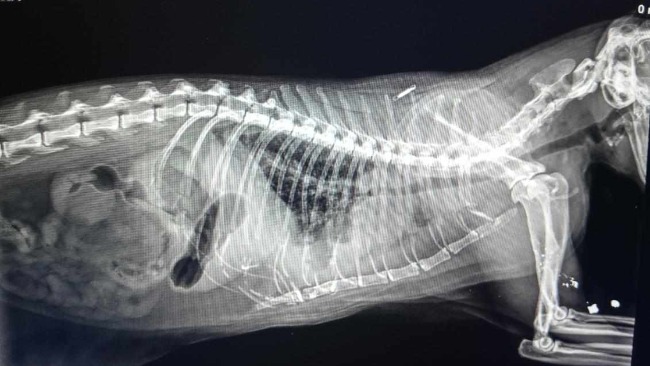

Wczoraj miał słabszy apetyt a dzisiaj rano drastycznie zaczęła mu spadać temperatura, poniżej 36 stopni. Natychmiast pojechał do lecznicy gdzie został poddany wstępnej diagnostyce, jednak ponieważ zaczął się u niego zbierać płyn w klatce piersiowej nieznanego pochodzenia i wystąpiła silna duszność musiałam go przewieźć na sygnale do lecznicy całodobowej. Tam trwa dalsza diagnostyka, zostało wykonane rtg, usg, zbadana krew ale nadal nie mamy przyczyny jego ciężkiego stanu.